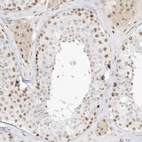

Immunohistochemical staining of human testis shows nuclear positivity in cells in seminiferous ducts.